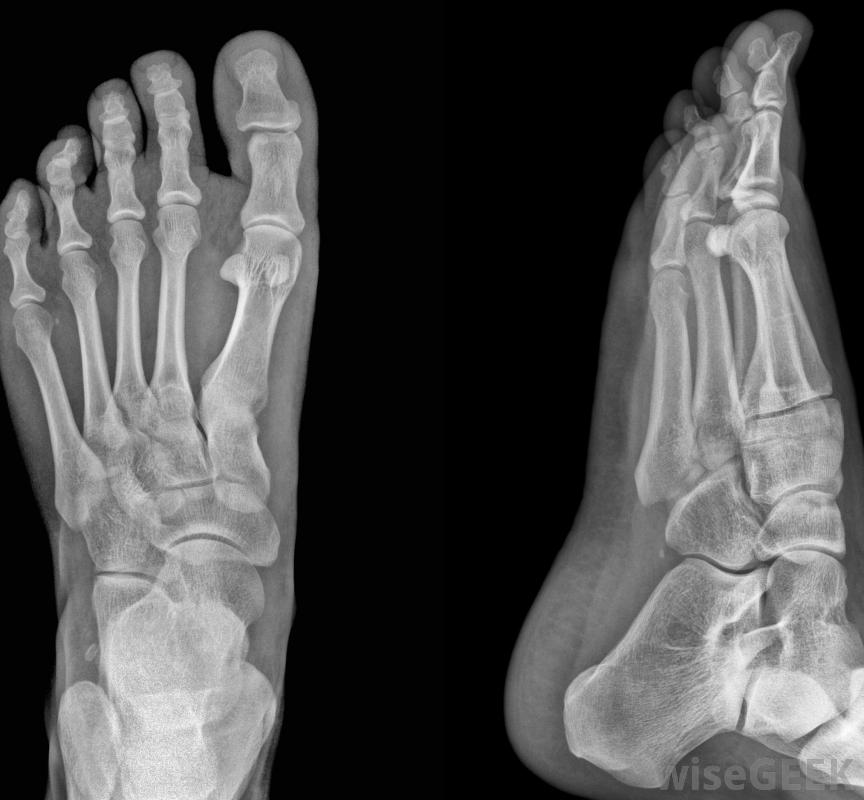

足部x光片可用于確認腳趾骨折。